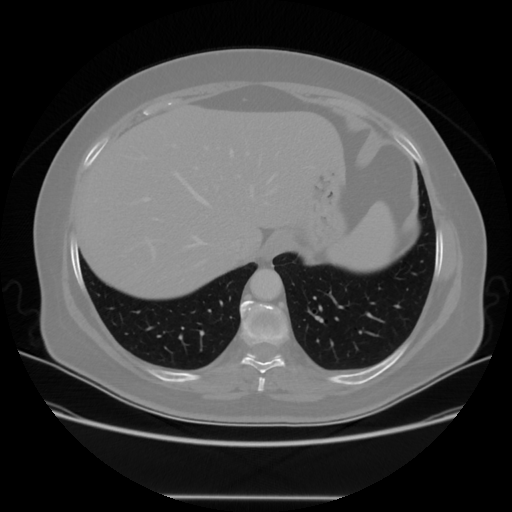

Generated VENOUS CT scan (A→B translation)

Full window (WL 1023.5, WW 4095 β†’ Low βˆ’1024, High +3071)

Lung window (WL -600, WW 1500 β†’ Low βˆ’1350, High +150)

Mediastinum window (WL 40, WW 400 β†’ Low βˆ’160, High +240)